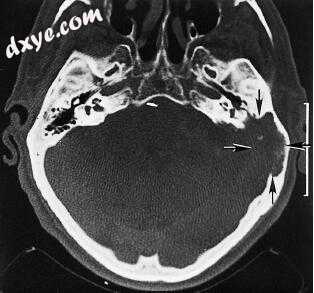

图-22. 一名82岁女性转移性乳腺癌的轴向计算机断层扫描显示大型溶解病变(箭头)破坏乳突,鳞状细胞,耳囊和迷路。

23.jpg